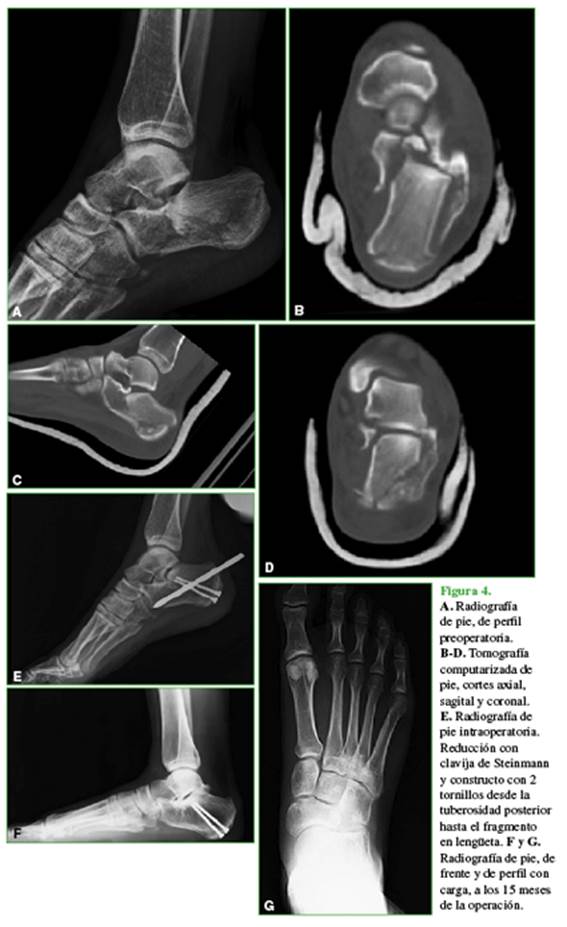

Antes de la cirugía, se realizó una tomografía computarizada multiplanar con cortes <1 mm, en los planos axial, sagital y semicoronales (ángulo de 30°) y reconstrucción 3D (Figura 1). Se usó la incidencia de Broden y axial de calcáneo intraoperatoria con intensificador de imágenes para constatar la reducción de la faceta posterior y el control de la osteosíntesis.8

Si la reducción de los ángulos de Böhler y de Gissane es buena, se procede a la estabilización con tornillos. Utilizamos diferentes opciones: 3,5 mm corticales; 4,0 mm esponjosa canulados; 6,5 mm esponjosa canulados y 5 mm bloqueados. El constructo depende del tamaño de los fragmentos y del patrón de la fractura evaluados antes de la reconstrucción 3D. En algunos casos, colocamos tornillos que fijen la lengüeta desde el nivel superoexterno y superomedial hasta la tuberosidad anterior, la tuberosidad posterior a la anterior (Figura 3) o desde la tuberosidad posterior hasta el fragmento en lengüeta (Figura 4).